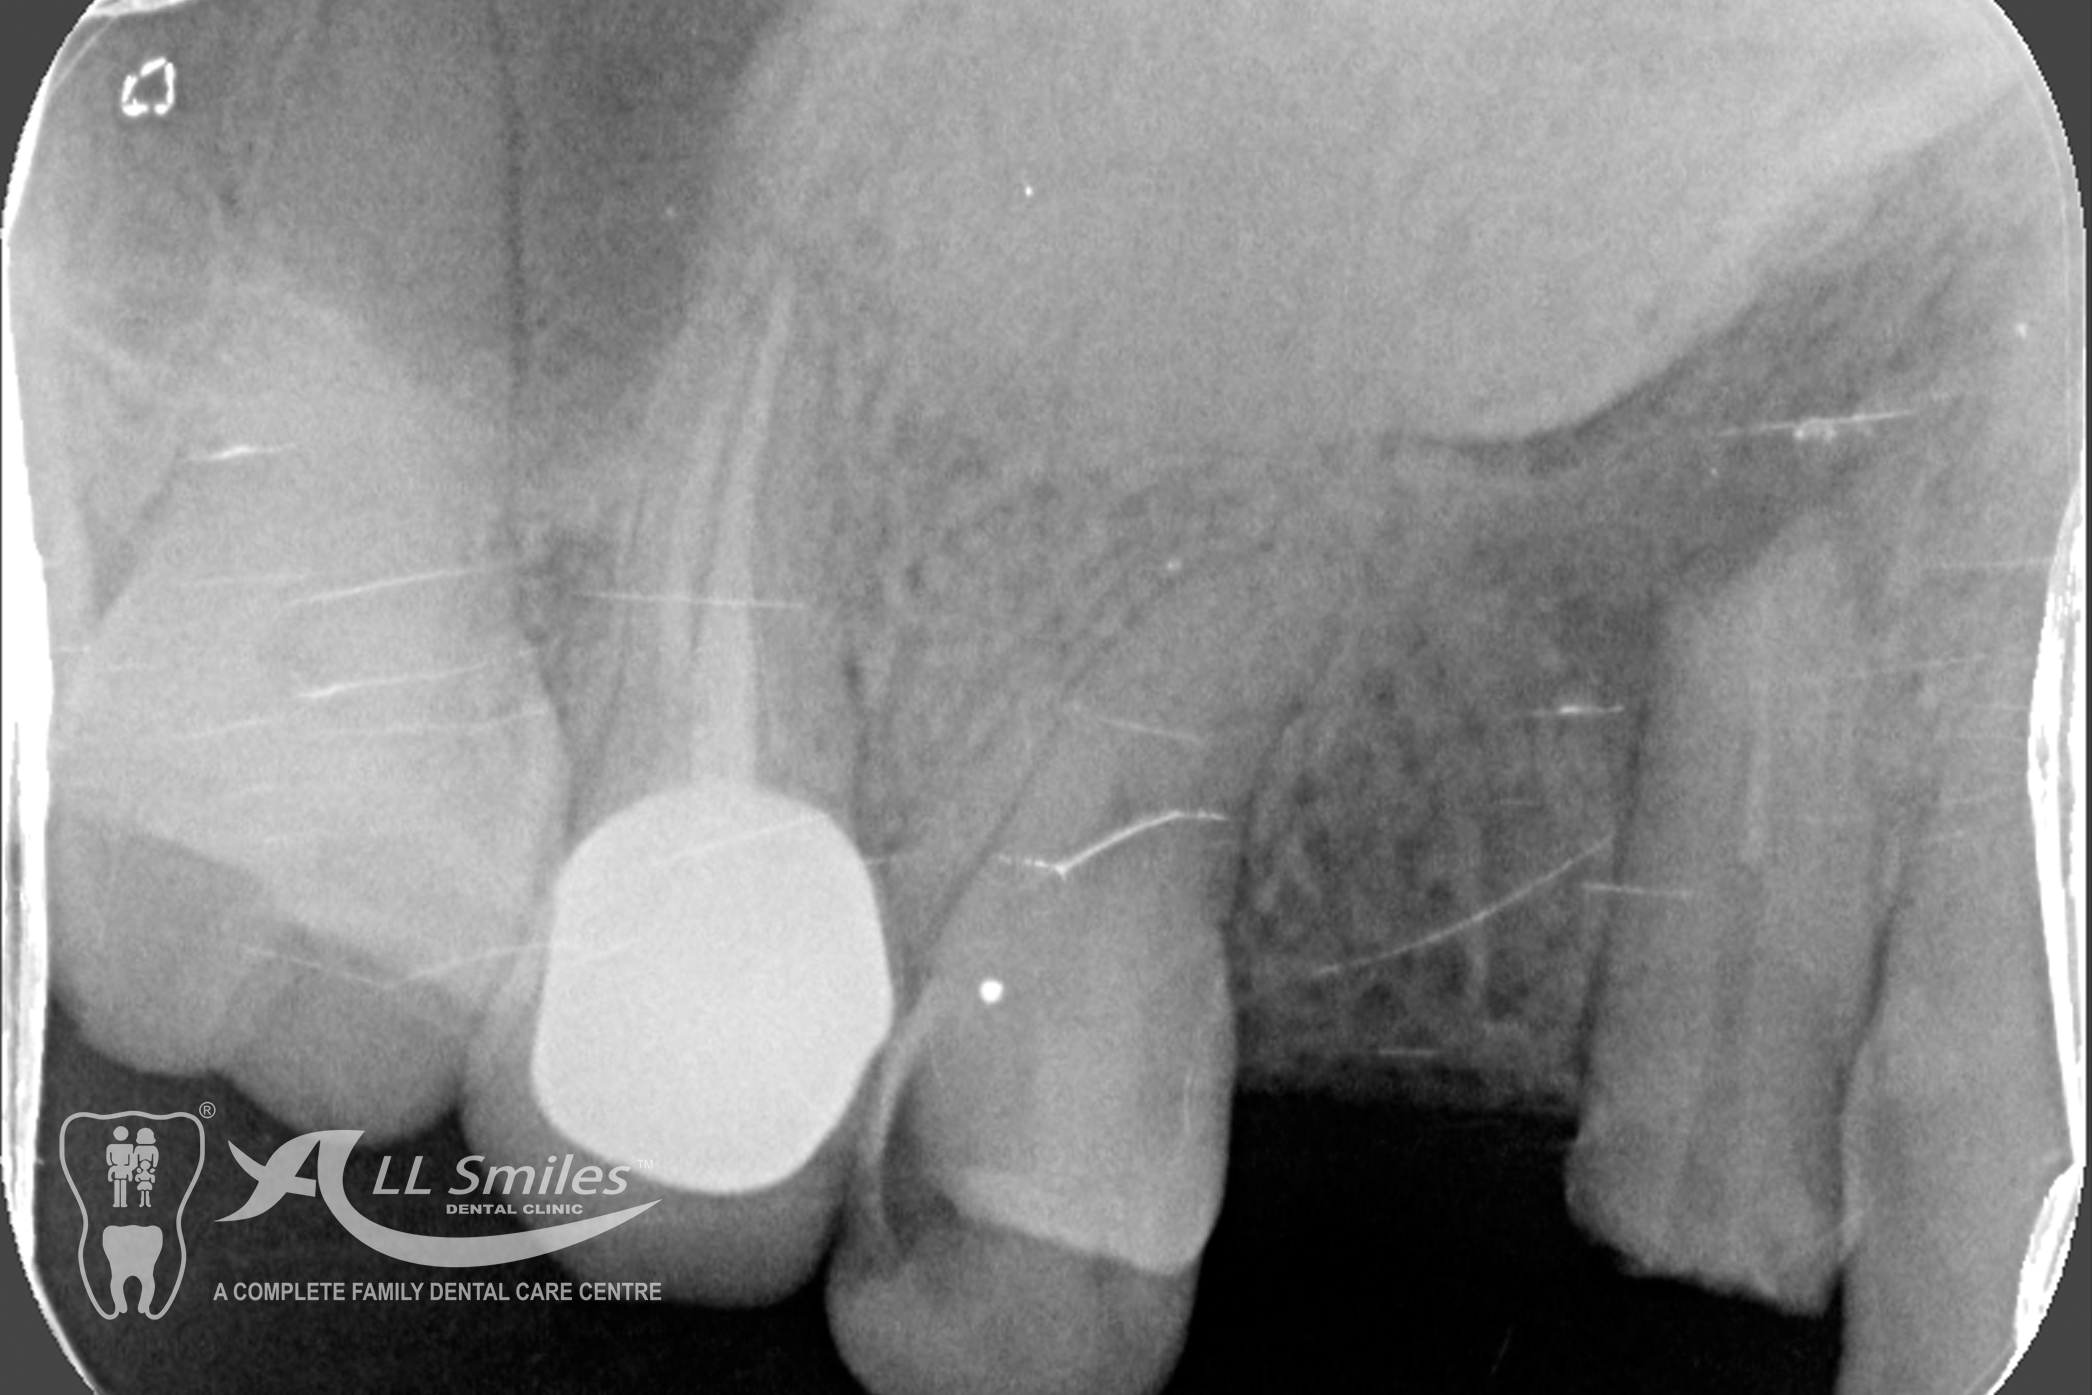

Root Canal Gallery